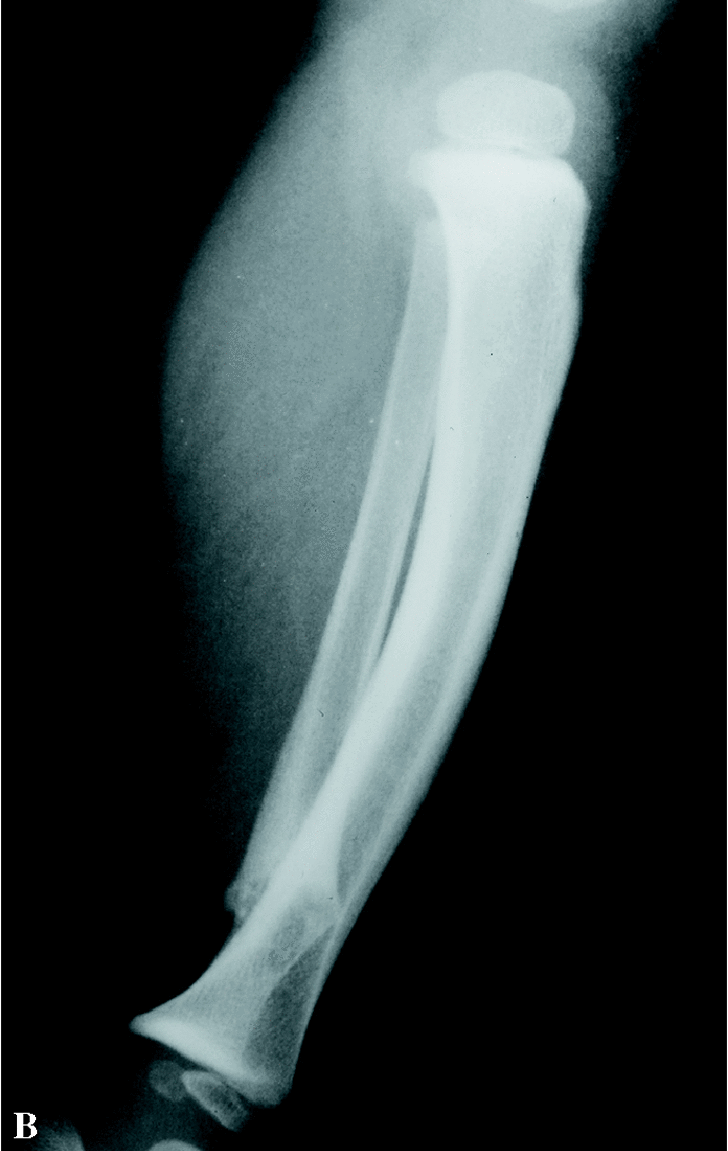

Paciente varón de 13 años que acude por primera vez a nuestras consultas con el diagnóstico previo de pseudoartrosis congénita de peroné con deformidad en valgo de tobillo derecho, sin una neurofibromatosis asociada. A los 16 meses de edad acudió al traumatólogo por tumoración en cara externa de tobillo derecho clínicamente asintomática. Tras realizar un estudio radiológico se diagnosticó de pseudoartrosis congénita de peroné (Fig. 1). Fue intervenido quirúrgicamente resecándose el foco de pseudoartrosis, sin aporte de injerto. A los 11 años, fue nuevamente valorado por presentar importante valgo de tobillo derecho; en la radiografía simple se apreció persistencia de pseudoartrosis peronea. Durante la cirugía se realizó una limpieza del tejido fibroso de la pseudoartrosis, añadiendo en esta ocasión injerto óseo de cresta iliaca, realizándose también una epifisiodesis medial de la tibia con tornillo AO (Fig. 2). Se inmovilizó con yeso. No mejora tras la cirugía.

Figura 1. Proyecciones antero-posterior (A) y lateral (B) de la tibia y el peroné derechos a los 16 meses de edad, en las que se aprecian la situación de la pseudoartrosis previa a cirugía.